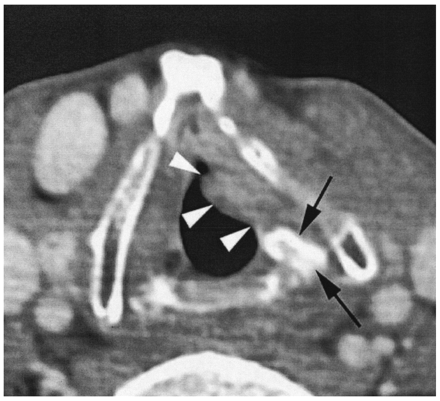

Axial contrast-enhanced CT image of a 67-year-old male patient with a glottic cancer (T2N0). A left-sided glottic soft tissue mass is seen (arrowheads). The tumor abuts the left arytenoid, which shows a clearly increased attenuation (arrows; compare with opposite side). Extended hemilaryngectomy was performed. No postoperative radiation therapy was administered. There is no evidence of disease 2 years after surgery.